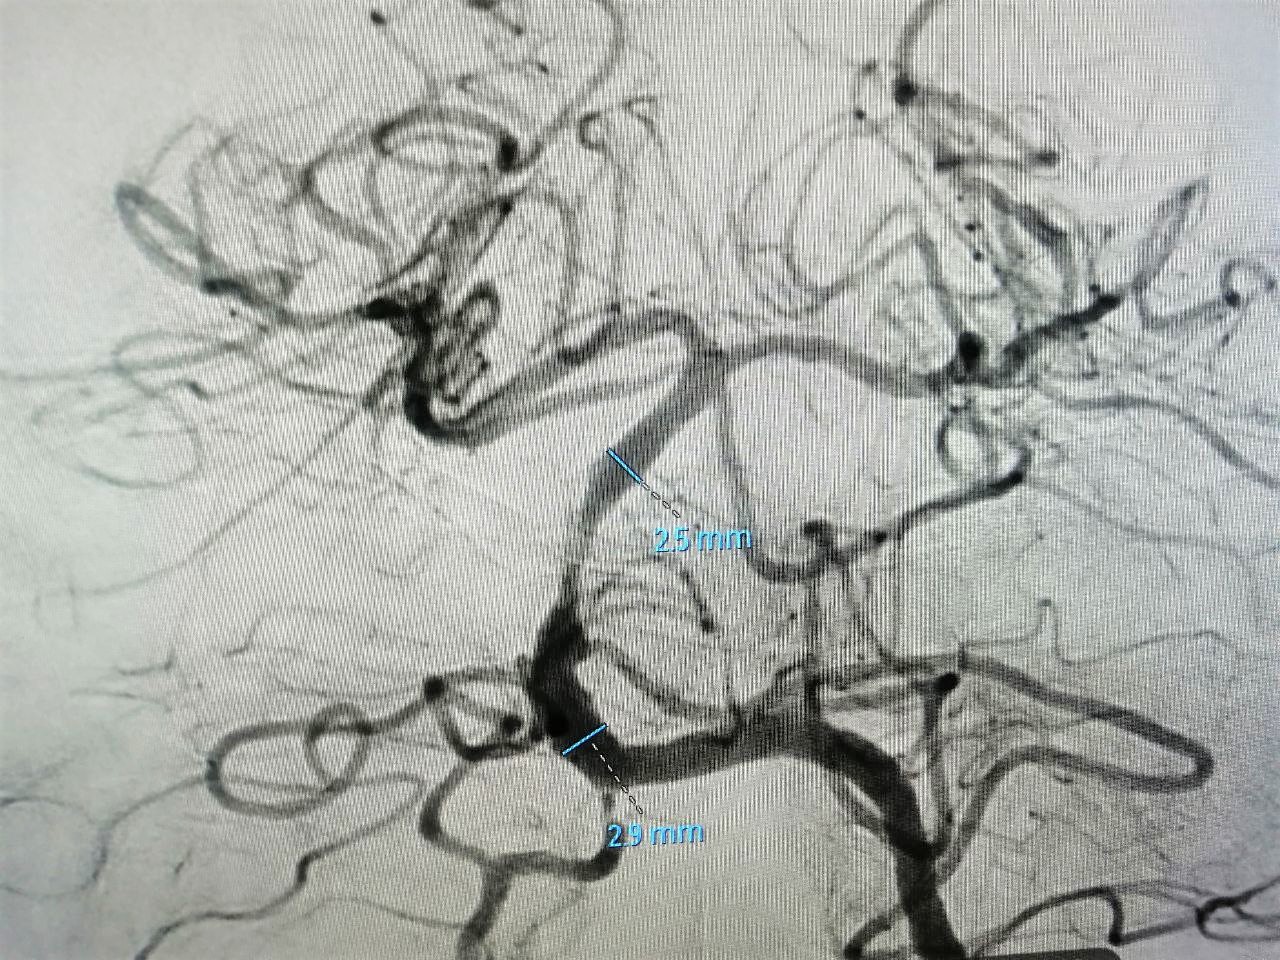

Специалист быстро удалил тромб. Но появившийся кровоток обозначил другую проблему – субокклюзию базилярной артерии. На участке длиной 8 миллиметров она представляла собой тонкую ниточку (фото №2). При таком сужении не только не возобновилось бы полноценное питание структур головного мозга, но и вновь образовался бы тромб. Причем, закупориваться просвет начал тут же, буквально на глазах рентгенохирурга.